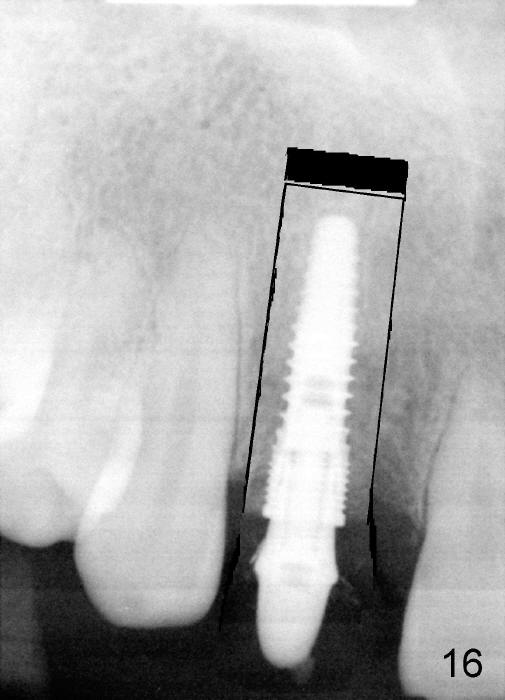

PA in Fig.15 is taken 1.5 months postop. It appears that there is enough space to make osteotomy around the implant (black outline) and move the segment coronally (Fig.16).